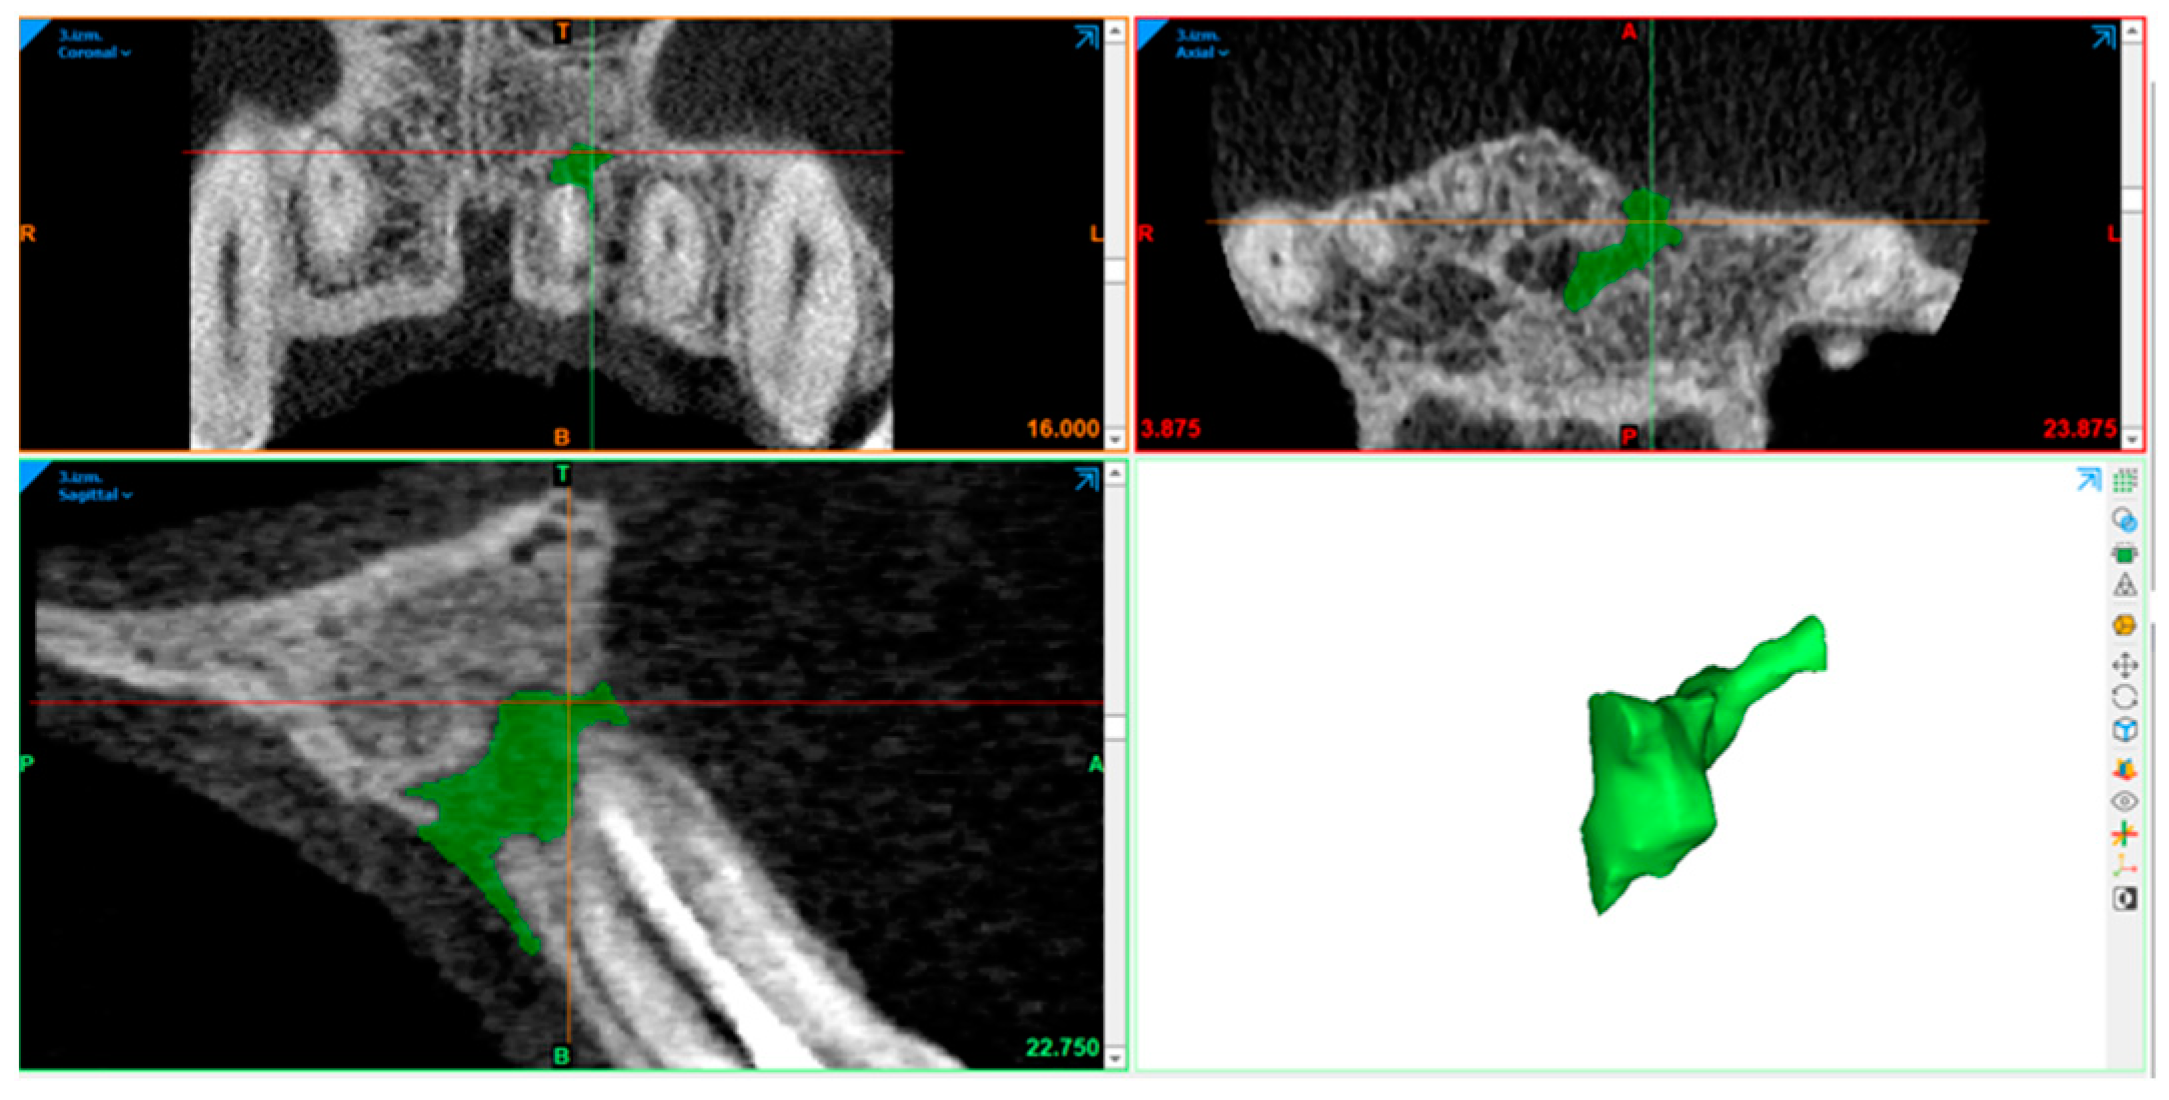

2.10. Radiography Acquisition: Volumetric Assessment

2.11. Statistical Analysis